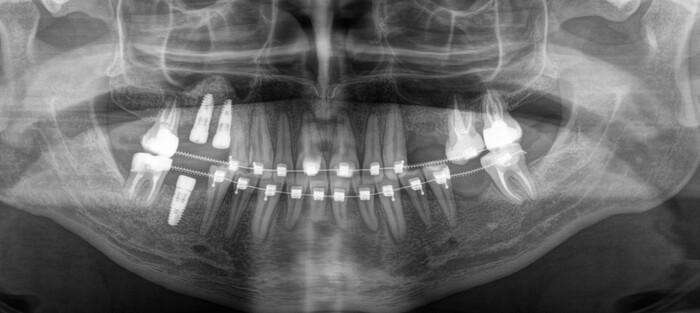

В процессе лечения 7-ой зуб на нижней челюсти треснул, появился скол, пришлось от него тоже избавиться. Ниже снимок с постоянными коронками и «внеплановым» имлпантатом:

Коронки на этом снимке уже четко различимы, потому что сделаны из керамики.

Вид «изнутри»:

Полость рта всё больше начинает преображаться.

Ещё один квантовый скачок и проходит 3.5 месяца. Выход на сцену временной коронки на имплантате, который был установлен позже остальных:

Вы её видите? И я не вижу. А она есть:

К моему великому сожалению, фотографии с финальным результатом у меня нет. Планировалось тотальное протезирование всех зубов и возможная замена постоянных коронок на имплантатах на другие, чуть более светлые.

«Сложный был год: налоги, катастрофы, проституция, бандитизм и недобор в армию…»

Тянуть больше с публикацией статьи я не могу, потому как уже выждал лишний месяц. К сожалению, Роман в ближайшее время не может попасть в клинику в связи с отъездом. Но я обещаю: по мере возможности обязательно добавлю конечный результат, как только он сможет приехать.

По большому счету на фото изменится лишь цвет постоянных коронок на имплантатах и появятся керамические коронки того же цвета на своих жевательных зубах.